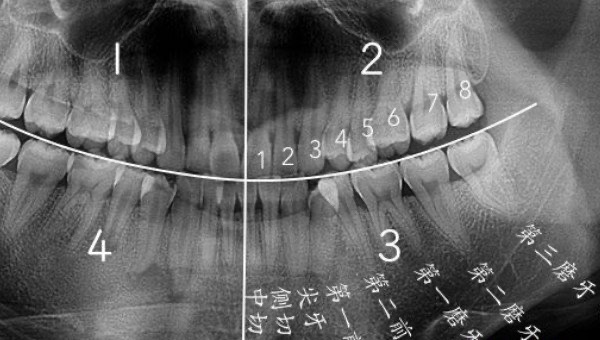

智齿是人类口腔内牙槽骨上最里面的第三颗磨牙,由于它经常会产生疼痛感,很多人选择将其拔掉,但部分人表示拔智齿后悔死了,那么这是为什么呢?快和小编去看看吧。

人在成年之后一般都会长智齿,在其生长期间可能会出现牙龈肿痛的情况,严重影响人们的日常生活,所以很多医生都建议将其拔掉,但总有人会因为拔掉后出现的不良反应而后悔。【趣元素】#叶赫那拉婉贞#事实上,智齿对人的危害没有那么大,如果其生长状态比较良好,则没有强行拔除的必要,除非是畸形智齿。